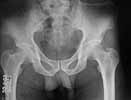

He has bilateral bicolumn acetabular fracture. At present on bilateral skin traction. I am attaching available images. CT of acetabulum planned after patient is out of ventilator.

Kindly give your valuable opinion on this patient's acetabular fractures. Should we plan bilateral bicolumn fixation(This would involve another set of major surgeries – two anteriorly and two posteriorly).